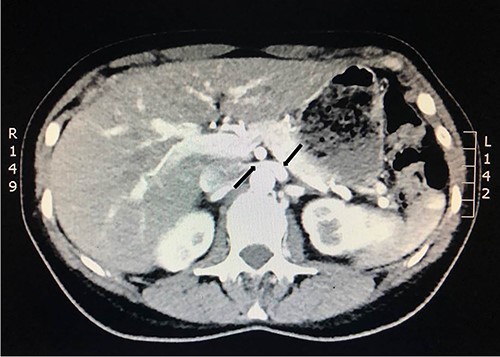

To investigate the bleeding source, she subsequently had a CT renal angiogram 3 days later that showed a narrow angle between origin of SMA and the aorta (Fig. 3) with multifocal areas of hypoattenuation throughout the left renal cortex (Fig. 4). It showed a compression ratio of 3.25 (diameter of pre-compressed vein =6.5 mm; diameter of compressed vein =2 mm) (Fig. 5).

Computed tomography angiogram on presentation showing pre-compressed LRV (right arrow); and compressed LRV (left arrow).

Computed tomography angiogram 6 months later showing pre-compressed LRV (right arrow); and compressed LRV (left arrow), but resolution of the congestion and swelling of the left kidney.